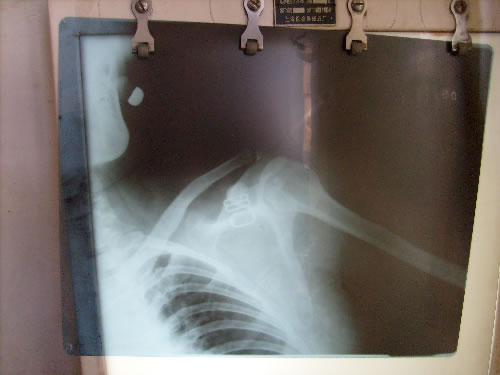

治愈前

姓名:郭风琴 女 49岁 烟台市 右肩关节脱位   2009年12月11日上午